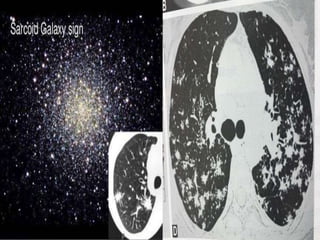

Uncommon findings:

– Conglomerate masses in a perihilar location.

– Larger nodules (> 1cm in diameter, in < 20%)

– Grouped nodules or coalescent nodules

surrounded by multiple satellite nodules (sarcoid

galaxy sign)